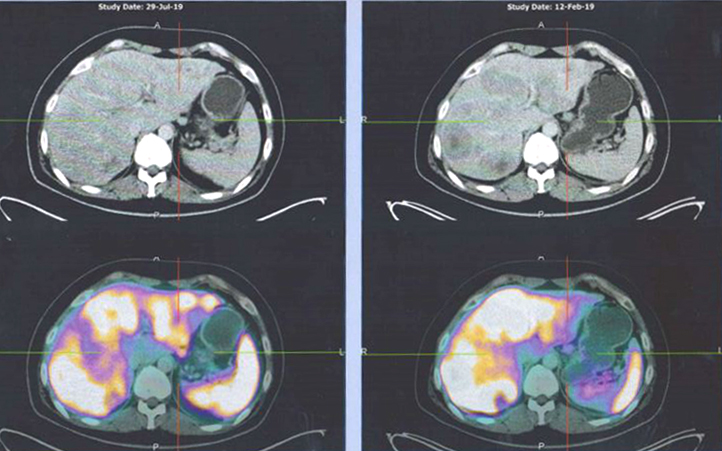

Let us look at the results of his PET scan.

Comparison of scan results: 29 July 2019 (left row) vs 12 February 2019 (right row)